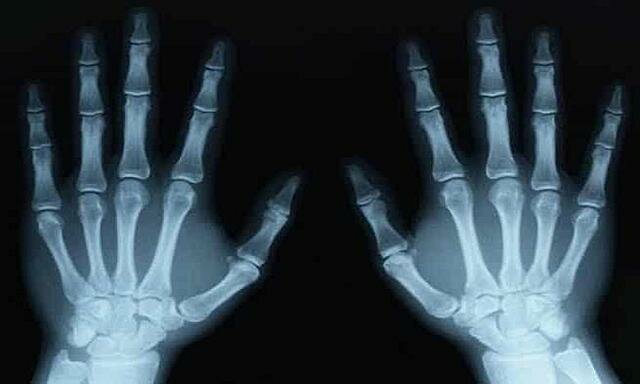

• Efectos biológicos de la radiación

Efectos biológicos de la radiación

Henri Bequerel en el año 1901, quien describió extrañas quemaduras en las manos tras manipular viales conteniendo radio

En 1917 en la Radium Corporation Factory en Orange, New Yersey, Estados Unidos se evidencio la trágica demostración de lo peligroso del radio cuando sus trabajadores comenzaron a sufrir severos trastornos físicos